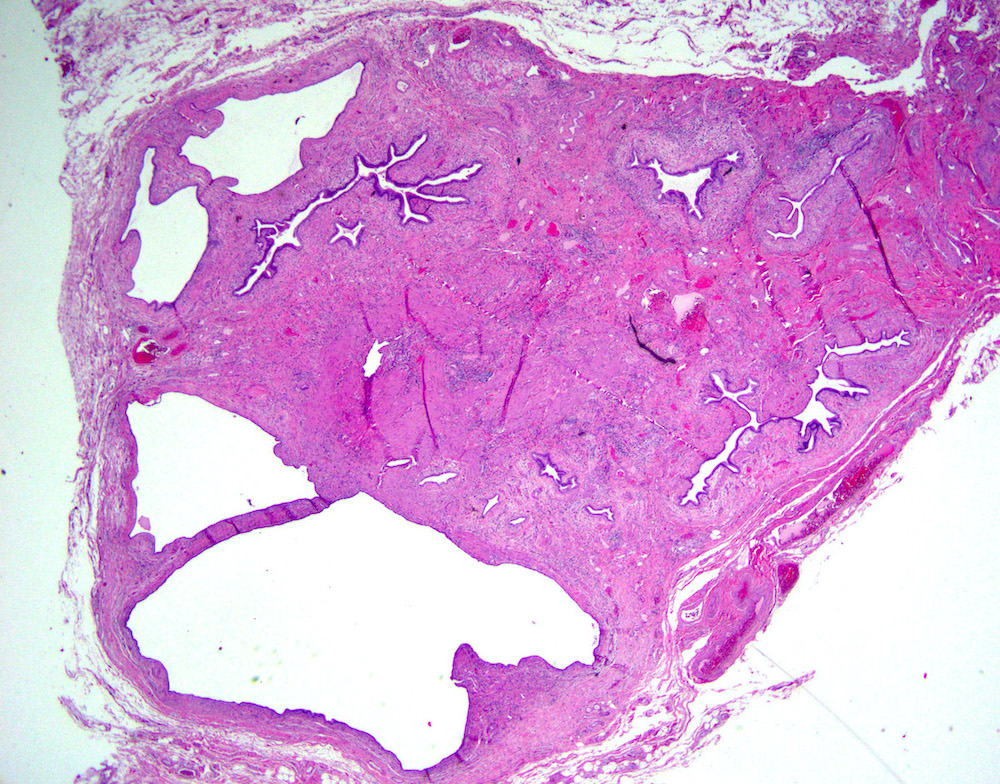

Microscopic (histologic) description

- Cystically dilated benign biliary glands accompanied by smooth muscle hypertrophy of gallbladder wall, thickened / fibrotic subserosa (StatPearls: Adenomyomatosis [Accessed 26 January 2021])

- Glands are distinct from the Rokitansky-Aschoff sinuses, which are epithelial diverticula, usually multifocal and occur throughout gallbladder secondary to injury, versus adenomyomatous nodule (distinct localized lesion of the gallbladder wall, 1 - 1.5 cm mural nodule in the fundus) (Am J Surg Pathol 2020;44:1649)

- May have reactive epithelial changes, papillary change and intestinal metaplasia (StatPearls: Adenomyomatosis [Accessed 26 January 2021])

- Rarely, benign glands are seen in proximity to nerves, appearing as perineural and intraneural invasion only in the subserosal layer (benign gland-like structures may migrate into nerves due to chemotactic factors or signaling substances with activation of cell receptors) (Am J Surg Pathol 2007;31:1598)

- Adenomyomatous nodules may rarely show dysplastic / carcinomatous transformation, whereas dysplasia in Rokitansky-Aschoff sinuses appears to be more common; however, the true association between adenomyomatous nodules and neoplasia has not yet been determined (Am J Surg Pathol 2020;44:1649)

- Recently, papillary dysplastic lesions of adenomyomas have been identified (intracholecystic neoplasms of adenomyomas), demonstrating cystic and solid areas with papillary projections that show biliary, gastric and intestinal phenotypes, with low or high grade dysplasia (Am J Surg Pathol 2020;44:1649)

Microscopic (histologic) images

Contributed by Monica T. Garcia-Buitrago, M.D.